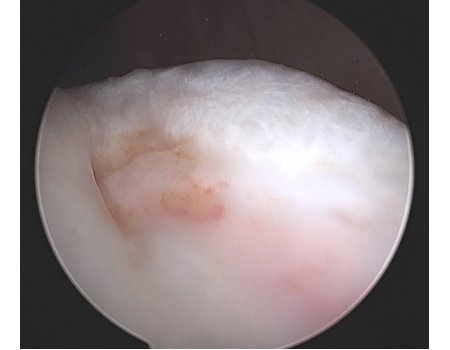

Open View of Chondral Lesion

Cored Recipient Trochlear Site